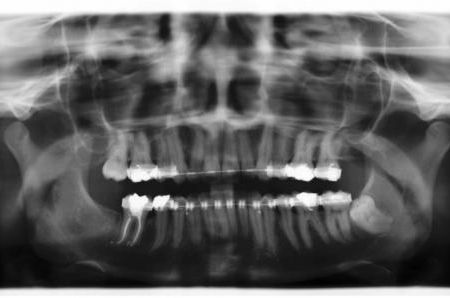

Röntgenbefunde

Links Röntgenbefund vor der Behandlung, rechts Zustand während der Behandlung. Die Lücke im Unterkiefer rechts (linke Seite auf dem Röntgenbild) wurde durch Vorbewegen und Aufrichten des endständigen (wurzelgefüllten) Backenzahnes geschlossen. Prothetische Maßnahmen wurden dadurch überflüssig, außerdem verbesserten sich die Verhältnisse für den Zahnhalteapparat dieses Zahnes deutlich. Der Weisheitszahn im Unterkiefer links wurde vor der chirurgischen Vorverlagerung des Unterkiefers entfernt, um eine ungünstige Trennung der Knochenfragmente zu vermeiden.